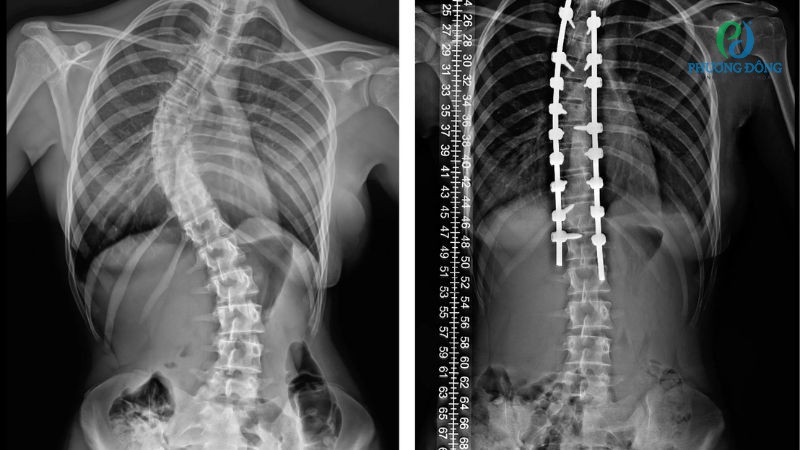

Phụ nữ bị vẹo cột sống vẫn có thể mang thai nhưng cần theo dõi thai kỳ sát sao